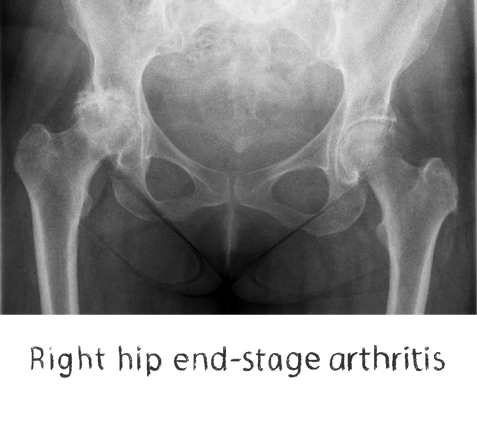

Plain film x-rays are taken to assess the joint

These are usually taken prior to your appointment. These help to confirm the diagnosis, assess the wear pattern and look for particular deformities. They can show old metalware and its position in the bone.

There are very few other surgical options for hip arthritis apart from hip replacement